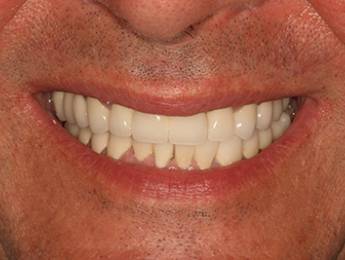

11. eset

27 éves páciensünk egész életében rettegett a fogorvosi beavatkozásoktól. Az összes foga elszuvasodott. A legkárosodottabb fogak gyökérkezelése és a szuvasodásainak megszűntetése után 26 fémkerámia koronát kapott a páciens. Erre a kezelésre is nagyon büszkék vagyunk. 2 hét leforgása alatt sikerült jelentős mértékben javítanunk a páciensünk mosolyán, önbizalmán és mióta velünk talalákozott, már a fogászati kezelésektől sem fél annyira!